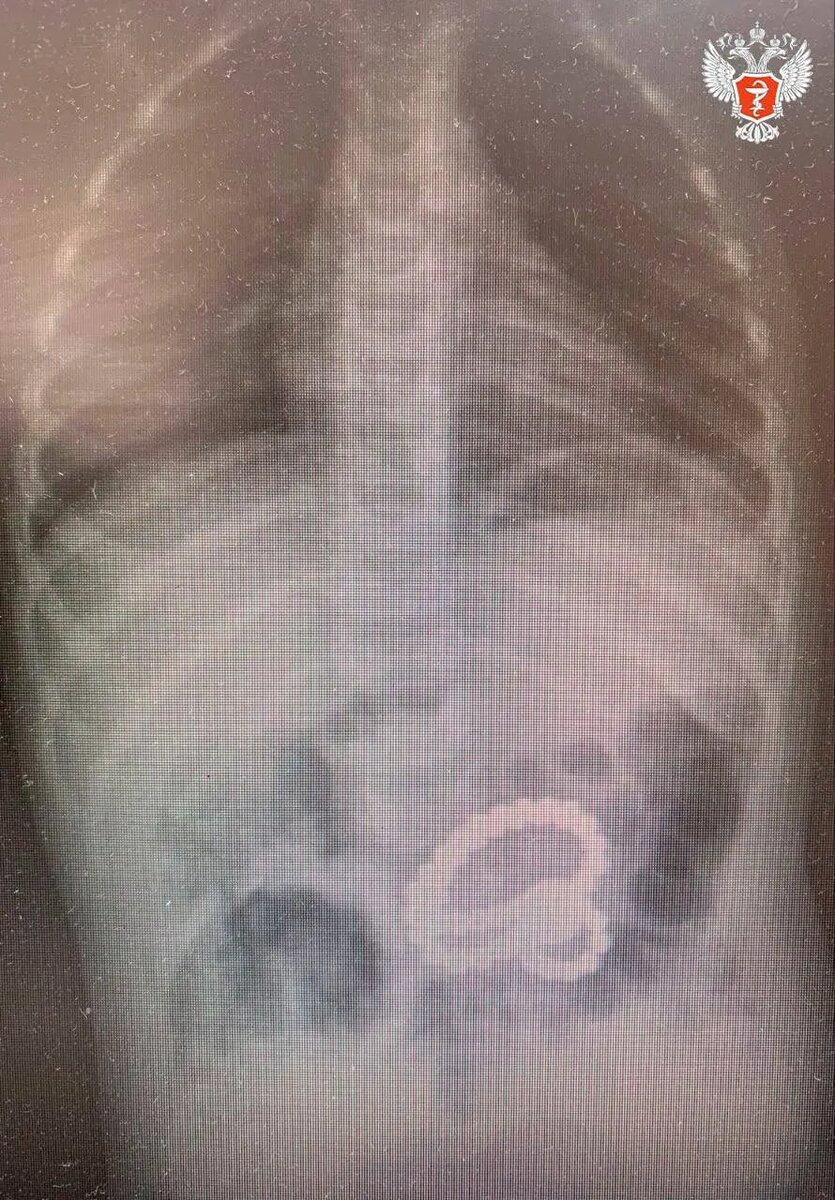

Маленький житель Воронежа проглотил почти пять десятков магнитных шариков и попал на операционный стол.

2-летний малыш поступил в Областную детскую клиническую больницу №2, где при обследовании желудка была обнаружена цепочка из более чем 40 магнитов. В ходе гастроскопии из маленького пациента последовательно извлекли 45 маленьких металлических шариков и один большой.

При этом еще три магнита остались внутри, извлечь их с помощью эндоскопа было невозможно. Медики удалили их через маленький разрез в брюшной стенке, рассказали в Минздраве Воронежской области.

Мальчик глотал магниты в разное время. Некоторые из них уже успели попасть в кишечник. Двигаясь по ЖКТ, магниты прицепились друг к другу и стянули стенки желудка и кишечника.